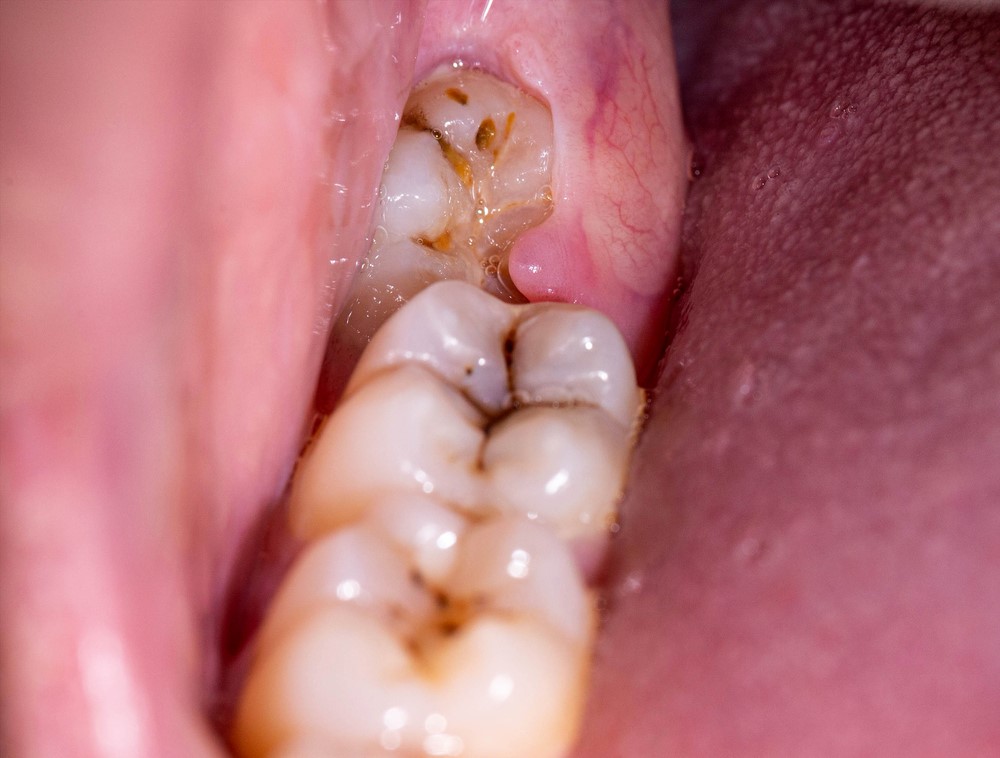

Hình ảnh về dấu hiệu nhận biết bạn đang bị viêm lợi trùm

Dấu hiệu nhận biết viêm lợi trùm thường khá rõ ràng và có thể bao gồm một số triệu chứng sau:

- Đau nhức: Cảm giác đau âm ỉ hoặc dữ dội ở vùng lợi quanh răng khôn, đặc biệt khi nhai hoặc chạm vào.

- Sưng tấy: Lợi có thể sưng đỏ và dễ chảy máu khi đánh răng hoặc sử dụng chỉ nha khoa.

- Mủ hoặc dịch: Xuất hiện mủ hoặc dịch nhầy ở khu vực lợi bị viêm, có thể gây khó chịu và tạo cảm giác không thoải mái.

- Hơi thở hôi: Vi khuẩn tích tụ có thể dẫn đến hơi thở có mùi hôi, làm giảm tự tin khi giao tiếp.

- Khó khăn khi mở miệng: Cảm giác cứng và khó khăn khi mở miệng rộng, đôi khi kèm theo cảm giác đau.